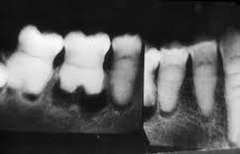

focal sclerosing osteomyelitis

-asymptomatic, bone adjacent to any tooth radiopaque area below roots -Mandibular 1st molar most common